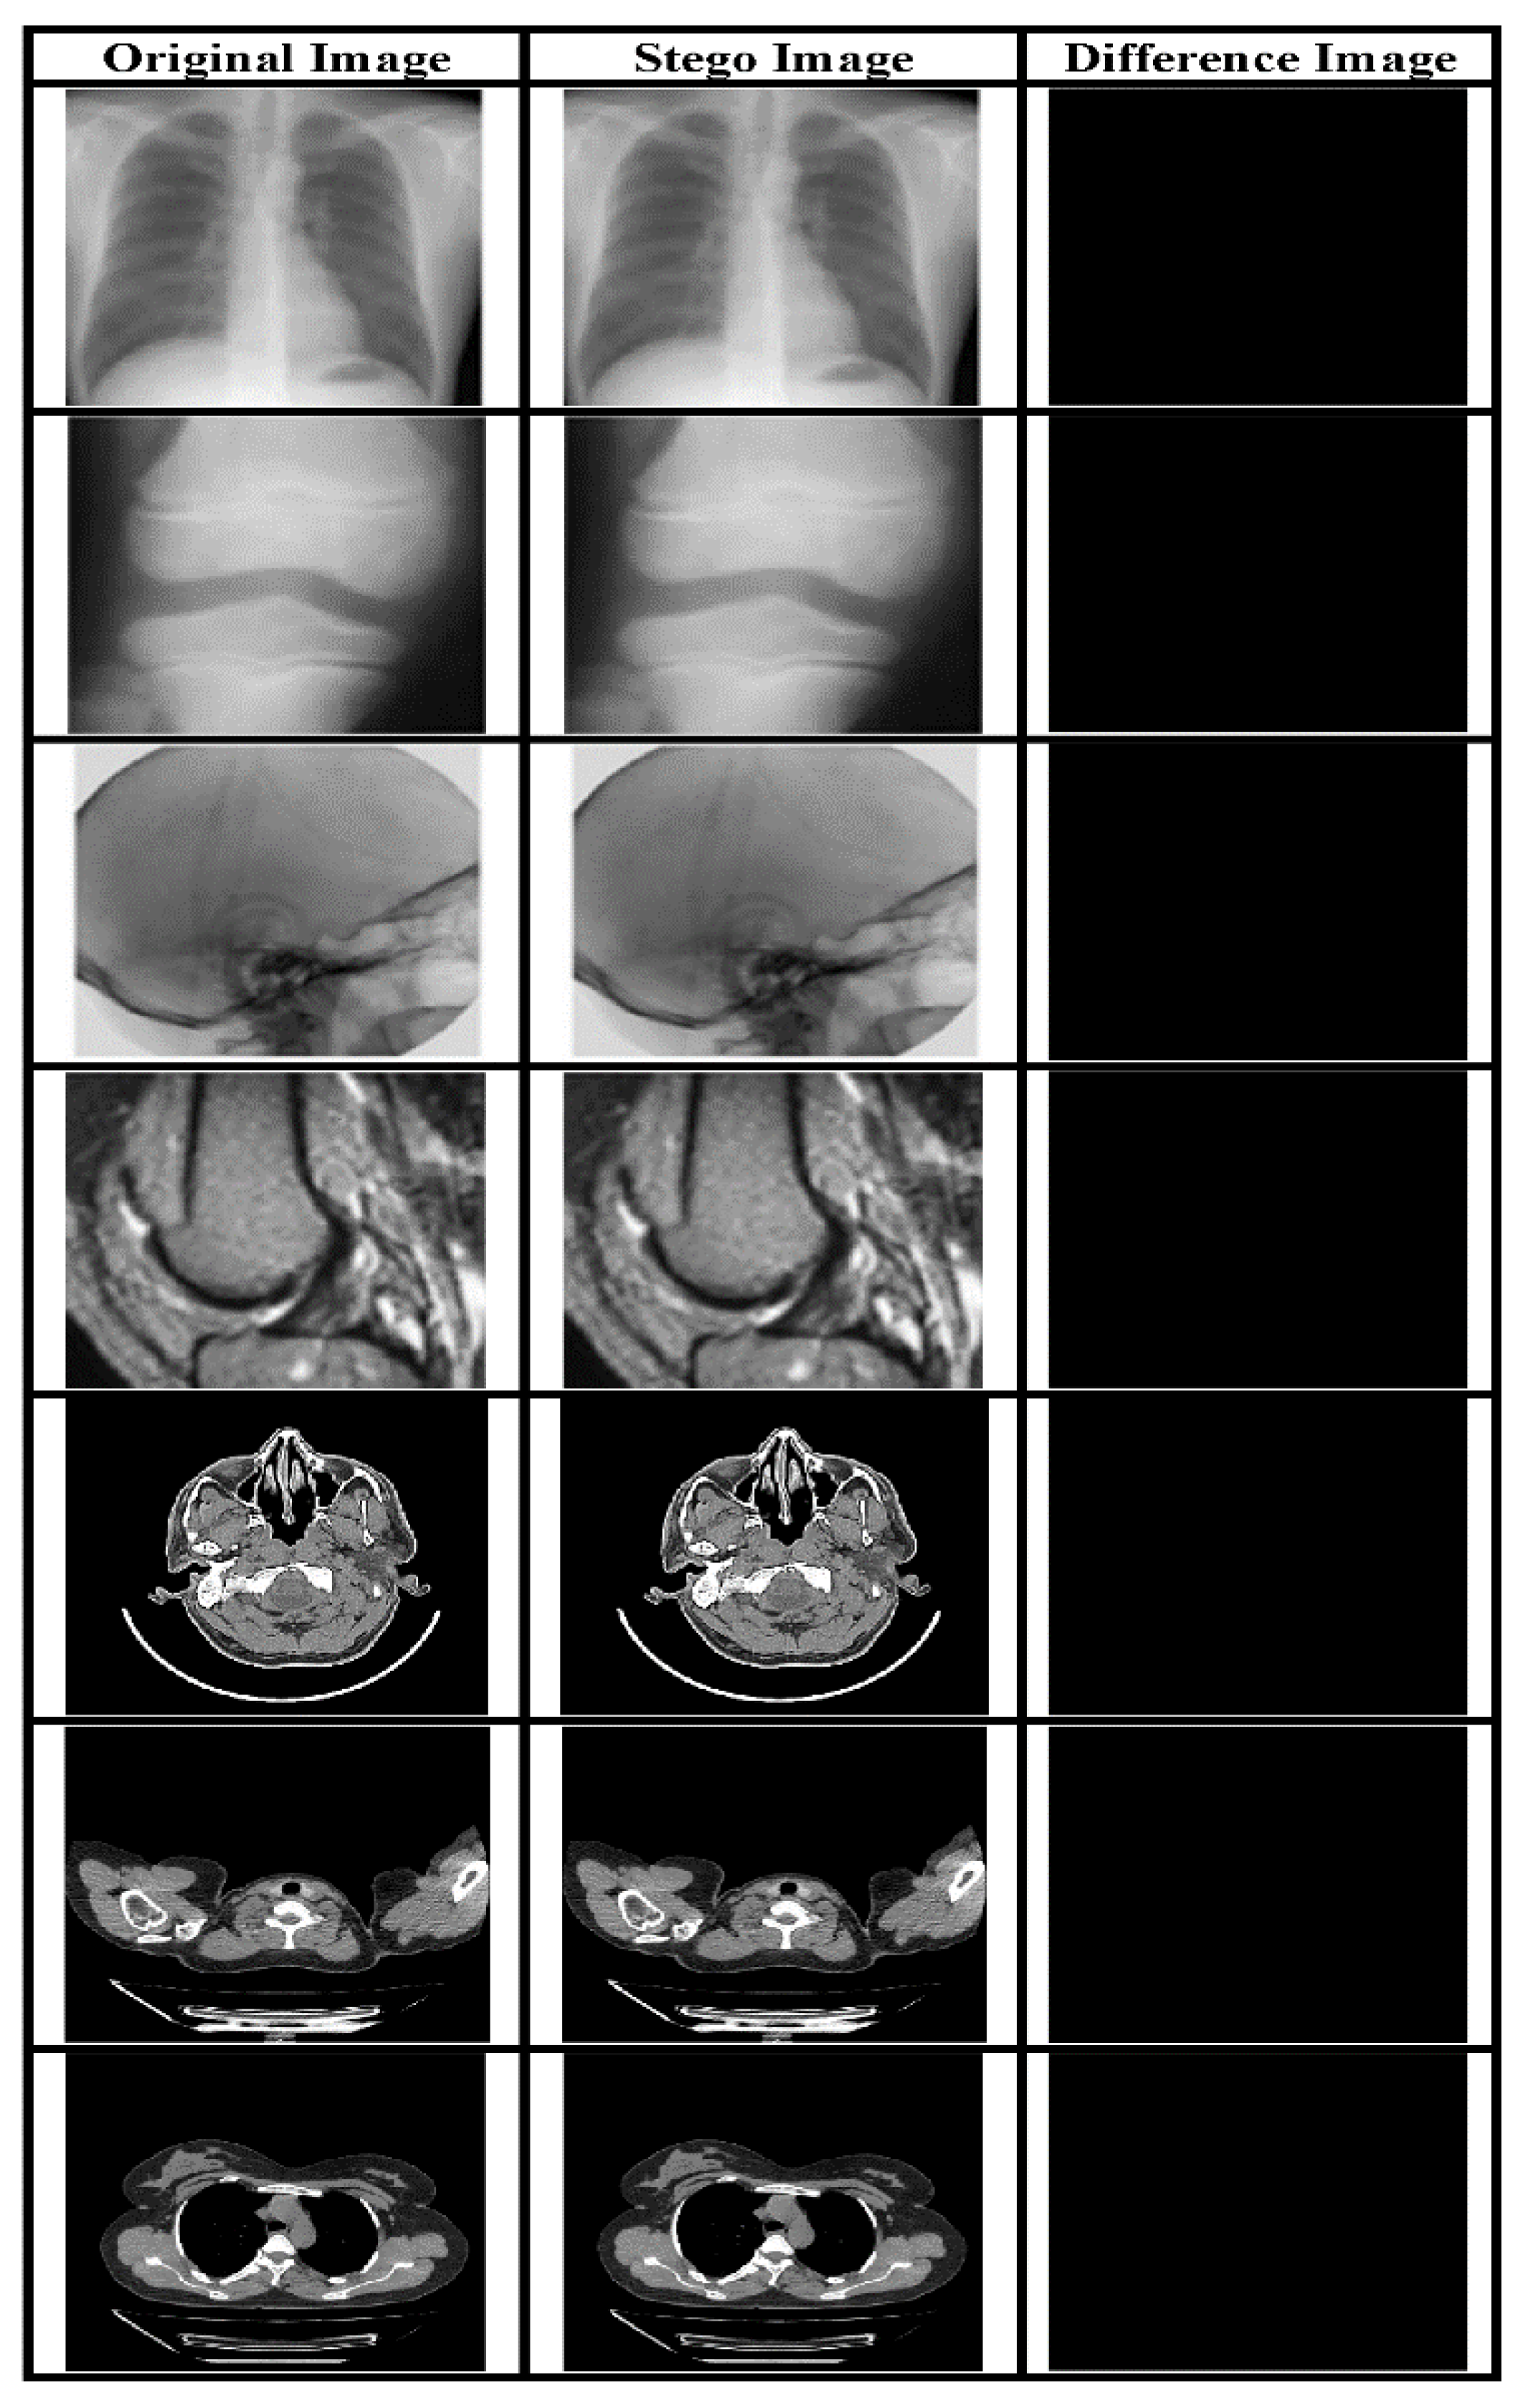

The payload is a critical underlying requirement of a data hiding system. The perceptual quality of the SI is evaluated using subjective and quality metrics like PSNR and it is a direct function of payload. In our proposed system we have embedded two types of data in the CI obtained using a novel IP method: EHR and watermark. Both types have been embedded using the LSB approach. The visual quality of the SI yielded by the embedding method is evaluated based on objective as well as subjective analysis. Figure 5 presents various original and Stego-MIs with a payload value equal to 0.75 bpp. The generated SI’s quality is much superior, along with high payload value. Furthermore, to validate the described RDH method a comparison has been made with contemporary works mentioned in [44] as shown in Figure 6 and Figure 7.

Figure 5.

MI with their corresponding SI for a payload of 0.75 bpp and the subtracted image.

The value of avg. PSNR for MI is 52.3756 dB whereas the avg. SSIM is 0.9849. This indicates that the scheme can yield high-quality images with a considerably high payload.

The PSNR2 and SSIM2 value for SI and the said payload is illustrated in Table 3.

Table 3 results depict that our system is capable of providing high visual quality images despite embedding an average payload of 0.75 bpp reversibly. This data embedding capacity is more than four times compared to 0.18 bpp [24]. Also, our scheme being implemented in the spatial domain is computationally less complex compared to [24].